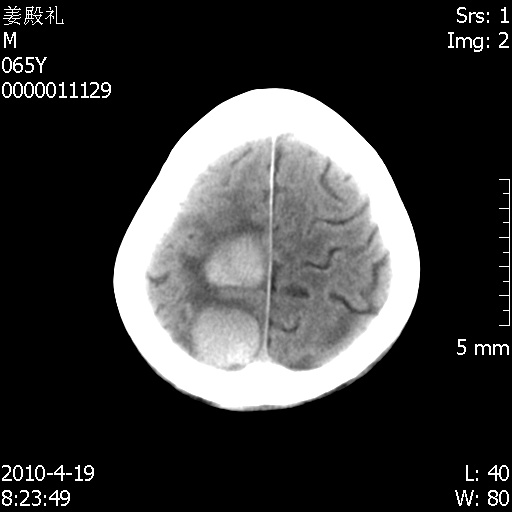

今天遇到临床医生,询问病人情况,病人已经死亡。

最后看到的病人右侧瞳孔呈针尖大小,估计是继发脑干梗死,而非脑疝死亡。

其他检查也没有来得及做。

遗憾! 复习了复查片:发现顶叶出血灶破入侧脑室,侧脑室体部见少许高密度。